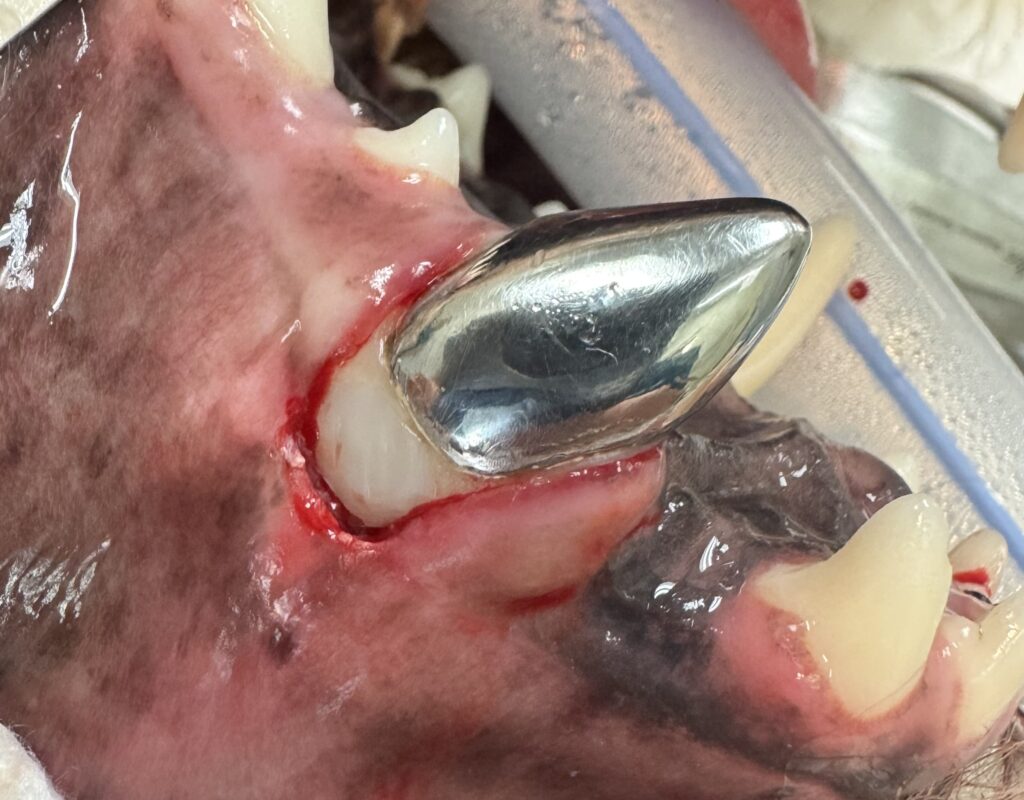

The tooth was treated with standard endodontic therapy (Figure 7) and prepared for a titanium crown (Figure 8). The client was instructed on home care and to recheck in 6 months.